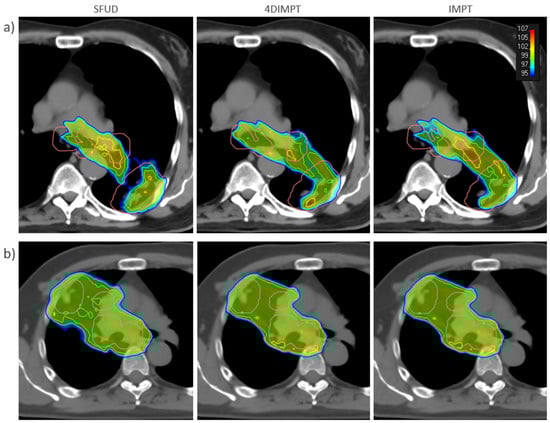

3.2. Target Coverage and OAR Sparing at Plan

3.3. Target Dose Robustness at Plan and Start

3.4. OAR Dose Robustness at Plan and Start

3.5. Target Coverage and OAR Sparing at Start